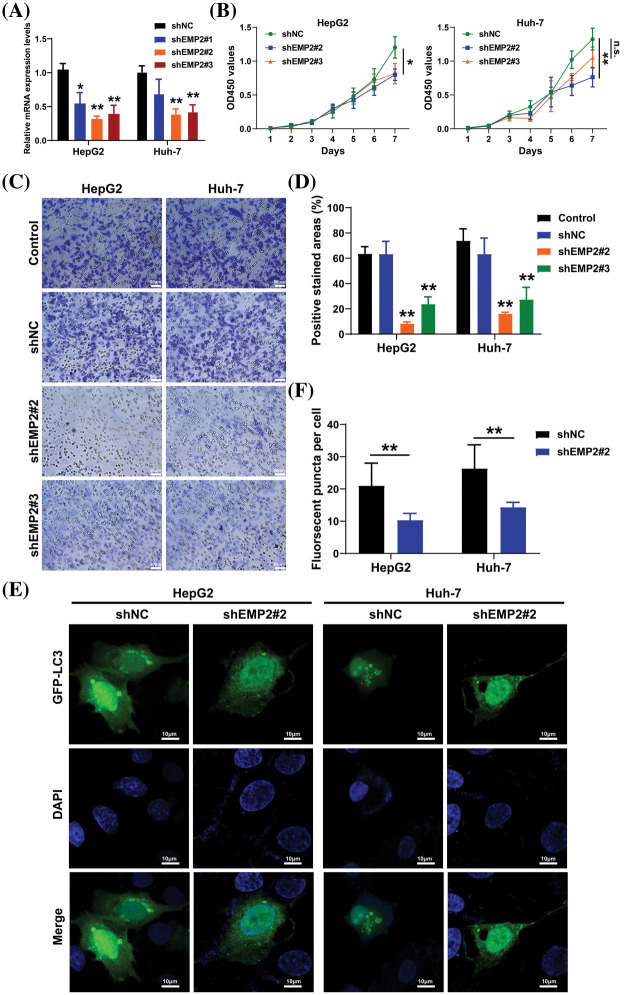

HepG2 and Huh-7 cells, which exhibited higher endogenous expression of EMP2, were selected, and shRNA-EMP2 lentiviral infection was conducted to screen for stable knockdown of EMP2 in HCC cell lines. The results showed that the three interfering sequences targeting EMP2 effectively reduced the expression of endogenous EMP2 mRNA in HepG2 and Huh-7 cells. In particular, sequences 2# and 3# exhibited relatively high interference efficiency, rendering them suitable for subsequent functional studies (Fig. 5A). Previous findings suggested a close correlation between high EMP2 expression and both clinical staging and prognosis of HCC. Moreover, the proliferative capacity of tumor cells plays a pivotal role in determining their degree of malignancy. To evaluate the impact of stable EMP2 knockdown on HCC cell lines (HepG2 and Huh-7), a CCK-8 assay was performed to measure their proliferation over time. The results showed that the growth curves of HepG2 cells transfected with stable 2# and 3# interference sequences initially overlapped with the control group. However, from day 6 onwards, a noticeable downward trend emerged, suggesting a moderate inhibition of proliferative capacity in the later stages of HepG2 cells (Fig. 5B). Moreover, compared to the blank control (Control) group and the negative control (shNC), stable knockdown of EMP2 expression in HepG2 and Huh-7 HCC cells (shEMP2#2 and shEMP2#3) significantly reduced the migration of tumor cells through the basement membrane and into the lower chamber. This indicates that silencing EMP2 can markedly decrease the invasive ability of both types of HCC cells, with the inhibitory effect being more pronounced for the 2# interference sequence (Figs. 5C, 5D).

Transient transfection of GFP-LC3 (green fluorescent protein-microtubule associated protein 1 light chain 3) plasmids was performed in HepG2 and Huh-7 HCC cells, and the punctate aggregation of GFP-LC3 fluorescence was observed using confocal microscopy. A significant reduction in the number of GFP-LC3 puncta was observed in the cytoplasm of the shEMP2 group compared to the control group, suggesting that downregulation of EMP2 expression in HepG2 and Huh-7 HCC cells substantially inhibits autophagy (Figs. 5E, 5F). To investigate the cellular ultrastructure, TEM was employed to observe cells in each group. The findings demonstrated that in HepG2 and Huh-7 HCC cells, the number of autophagosomes in the shEMP2#2 group cells was significantly reduced compared to the control group, further corroborating the concept that downregulation of EMP2 expression inhibits autophagy in HCC cells (Fig. 6A). Furthermore, Annexin-V/PI (Propidium Iodide) dual-staining flow cytometry was utilized to assess apoptosis in HepG2 cells following EMP2 silencing. The results demonstrated that cellular apoptosis did not exhibit a significant increase in the EMP2 knockdown group compared to the control group of HepG2 cells (Fig. 6B). These findings suggest that although EMP2 silencing inhibited the proliferative capacity and autophagy in HCC cells, it did not trigger cellular apoptosis.